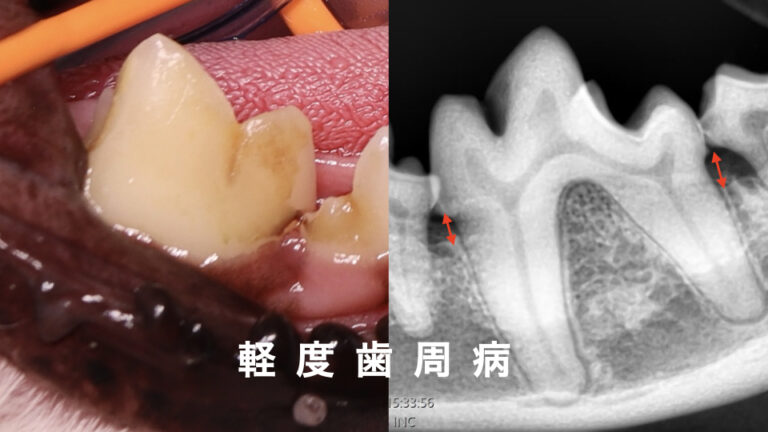

歯が欠けてしまい、神経(歯髄)が出てしまった状態を露髄と言います。

露髄が起こってしまうと、細菌が歯の内部に侵入し、細菌感染が起き、歯髄は壊死し、症状が進むと根の先の炎症「根尖性歯周炎」が起きてします。

また、露髄はしなくても歯が欠けて内部の象牙質が露出してしまうと、知覚過敏などの症状につながると言われています。

露髄を伴わない場合は歯冠修復が適応となります。

露髄を伴う場合、生活歯髄切断、抜髄治療、抜歯が適応になります。